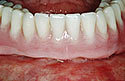

The modified denture ready for seating.

The patient's denture seated.